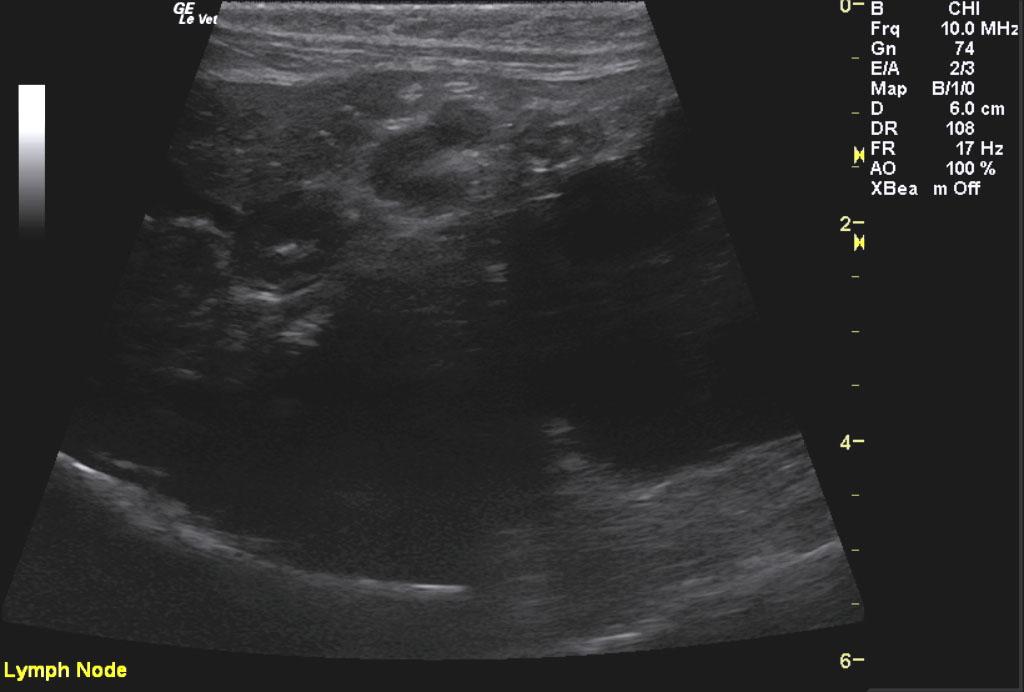

Kidney Mass – the findings are severe -DDx: primary renal carcinoma, primary renal TCC, renal lymphosarcoma – may appear as diffuse disease or focal mass. Less likely: renal malignant histiocytosis or mastocytosis, malignant osteosarcoma, hemangiosarcoma . 2) Liver – the findings are moderately-severe – DDx: a) Hepatic lipidosis / Cholangiohepatitis b) Infiltrative neoplasia (lymphoma – probable in this case) c) Chronic vs. Acute hepatitis or cholangiohepatitis (bacterial vs. sterile vs. toxin) 3) Lymph nodes – the findings are moderate – DDx: infiltrative neoplasia is likely vs. reactive Due to the involvement of the liver, gastrointestinal tract, and multiple enlarged lymph nodes, lymphosarcoma is a highly likely.

Image 1 & Video 1: The liver was moderately enlarged, rounded in shape having mildly hypoechoic echogenicity with multifocal hypoechoic and cystic nodules throughout. The gallbladder was normal in size, shape, and clean. Images 2-4 & Video 2-4: The left and right kidneys were severely enlarged with mild hydronephrosis in the right kidney. Both kidneys had hyperechoic cortices with large hypoechoic caps surrounding and invading the renal cortices (left kidney cap-7.4 mm in thickness, right kidney cap-13.6 mm in thickness). Image 5 & Video 5: Stomach: mucosal layer is mild/moderately thickened with overall wall thickness measuring 3.8 mm. Images 6: Intestine: there is focal mucosal layer thickening measuring up to 5.1 mm while the rest of the intestinal loops are of normal thickness. Video 6: Colon: the colonic wall appeared thickened at the ileocecolcolic junction. Image 7: Lymph Nodes: Multiple mesenteric lymph nodes were severely enlarged throughout the abdomen. The epigastric LN enlargement is shown in this image in the near field.